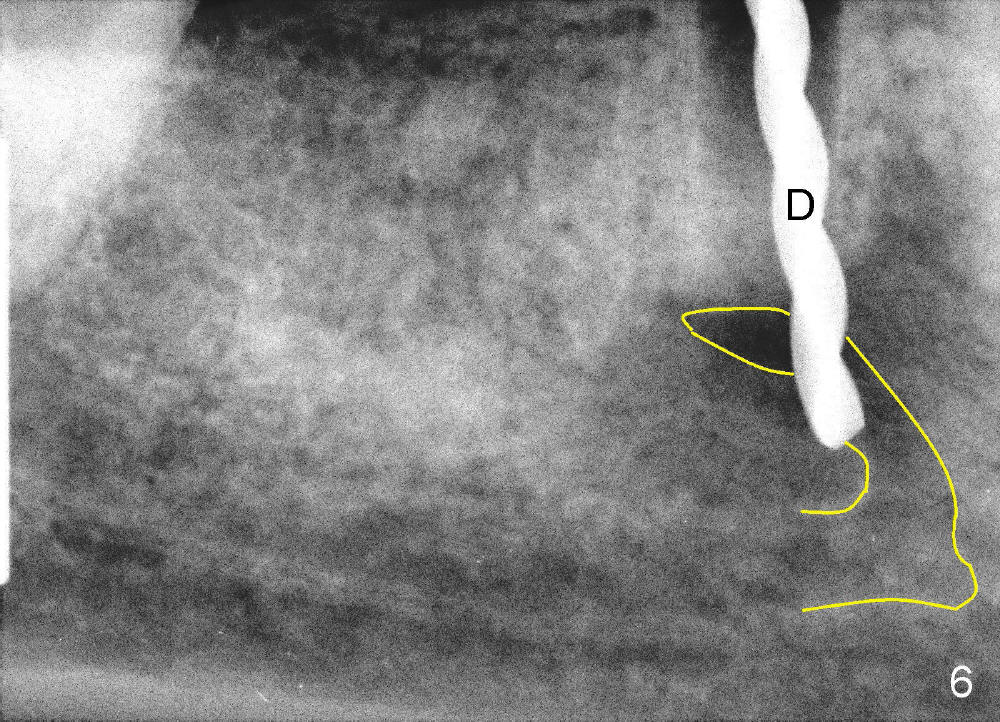

A 49-year-old lady cannot chew with the lower right bridge (Fig.1: from the 2nd premolar (5) to the third molar (8)). Insertion of gutta percha (Fig.2 >) points to the apical radiolucency of the anterior abutment (*). The bridge is sectioned between the pontic of 2nd molar and the retainer of the posterior abutment. The anterior segment of the bridge falls out. The anterior abutment is non-salvageable due to severe 2nd caries (Fig.3 (5) part of panaramic X-ray). The yellow lines denote the inferior alveolar nerve. In brief, the apex of the affected tooth is most likely closely associated with the mental loop.

If the immediate implant (5x20 mm) is placed within the confinement of the socket, the integrity of the nerve will be not violated (Fig.4). The patient returns for the surgery 2 months after bridge removal. The root stump is cleaned so well that the buccal apical fistula disappears (Fig.5). The mesiodistal dimension of the root is 5 mm, whereas buccolingual 6.5 mm. Infiltration (not block) anesthesia is administered. The root is extracted. A 2 mm pilot drill drops by itself into the socket (Fig.6 D); the loop should overlap the apex of the socket.